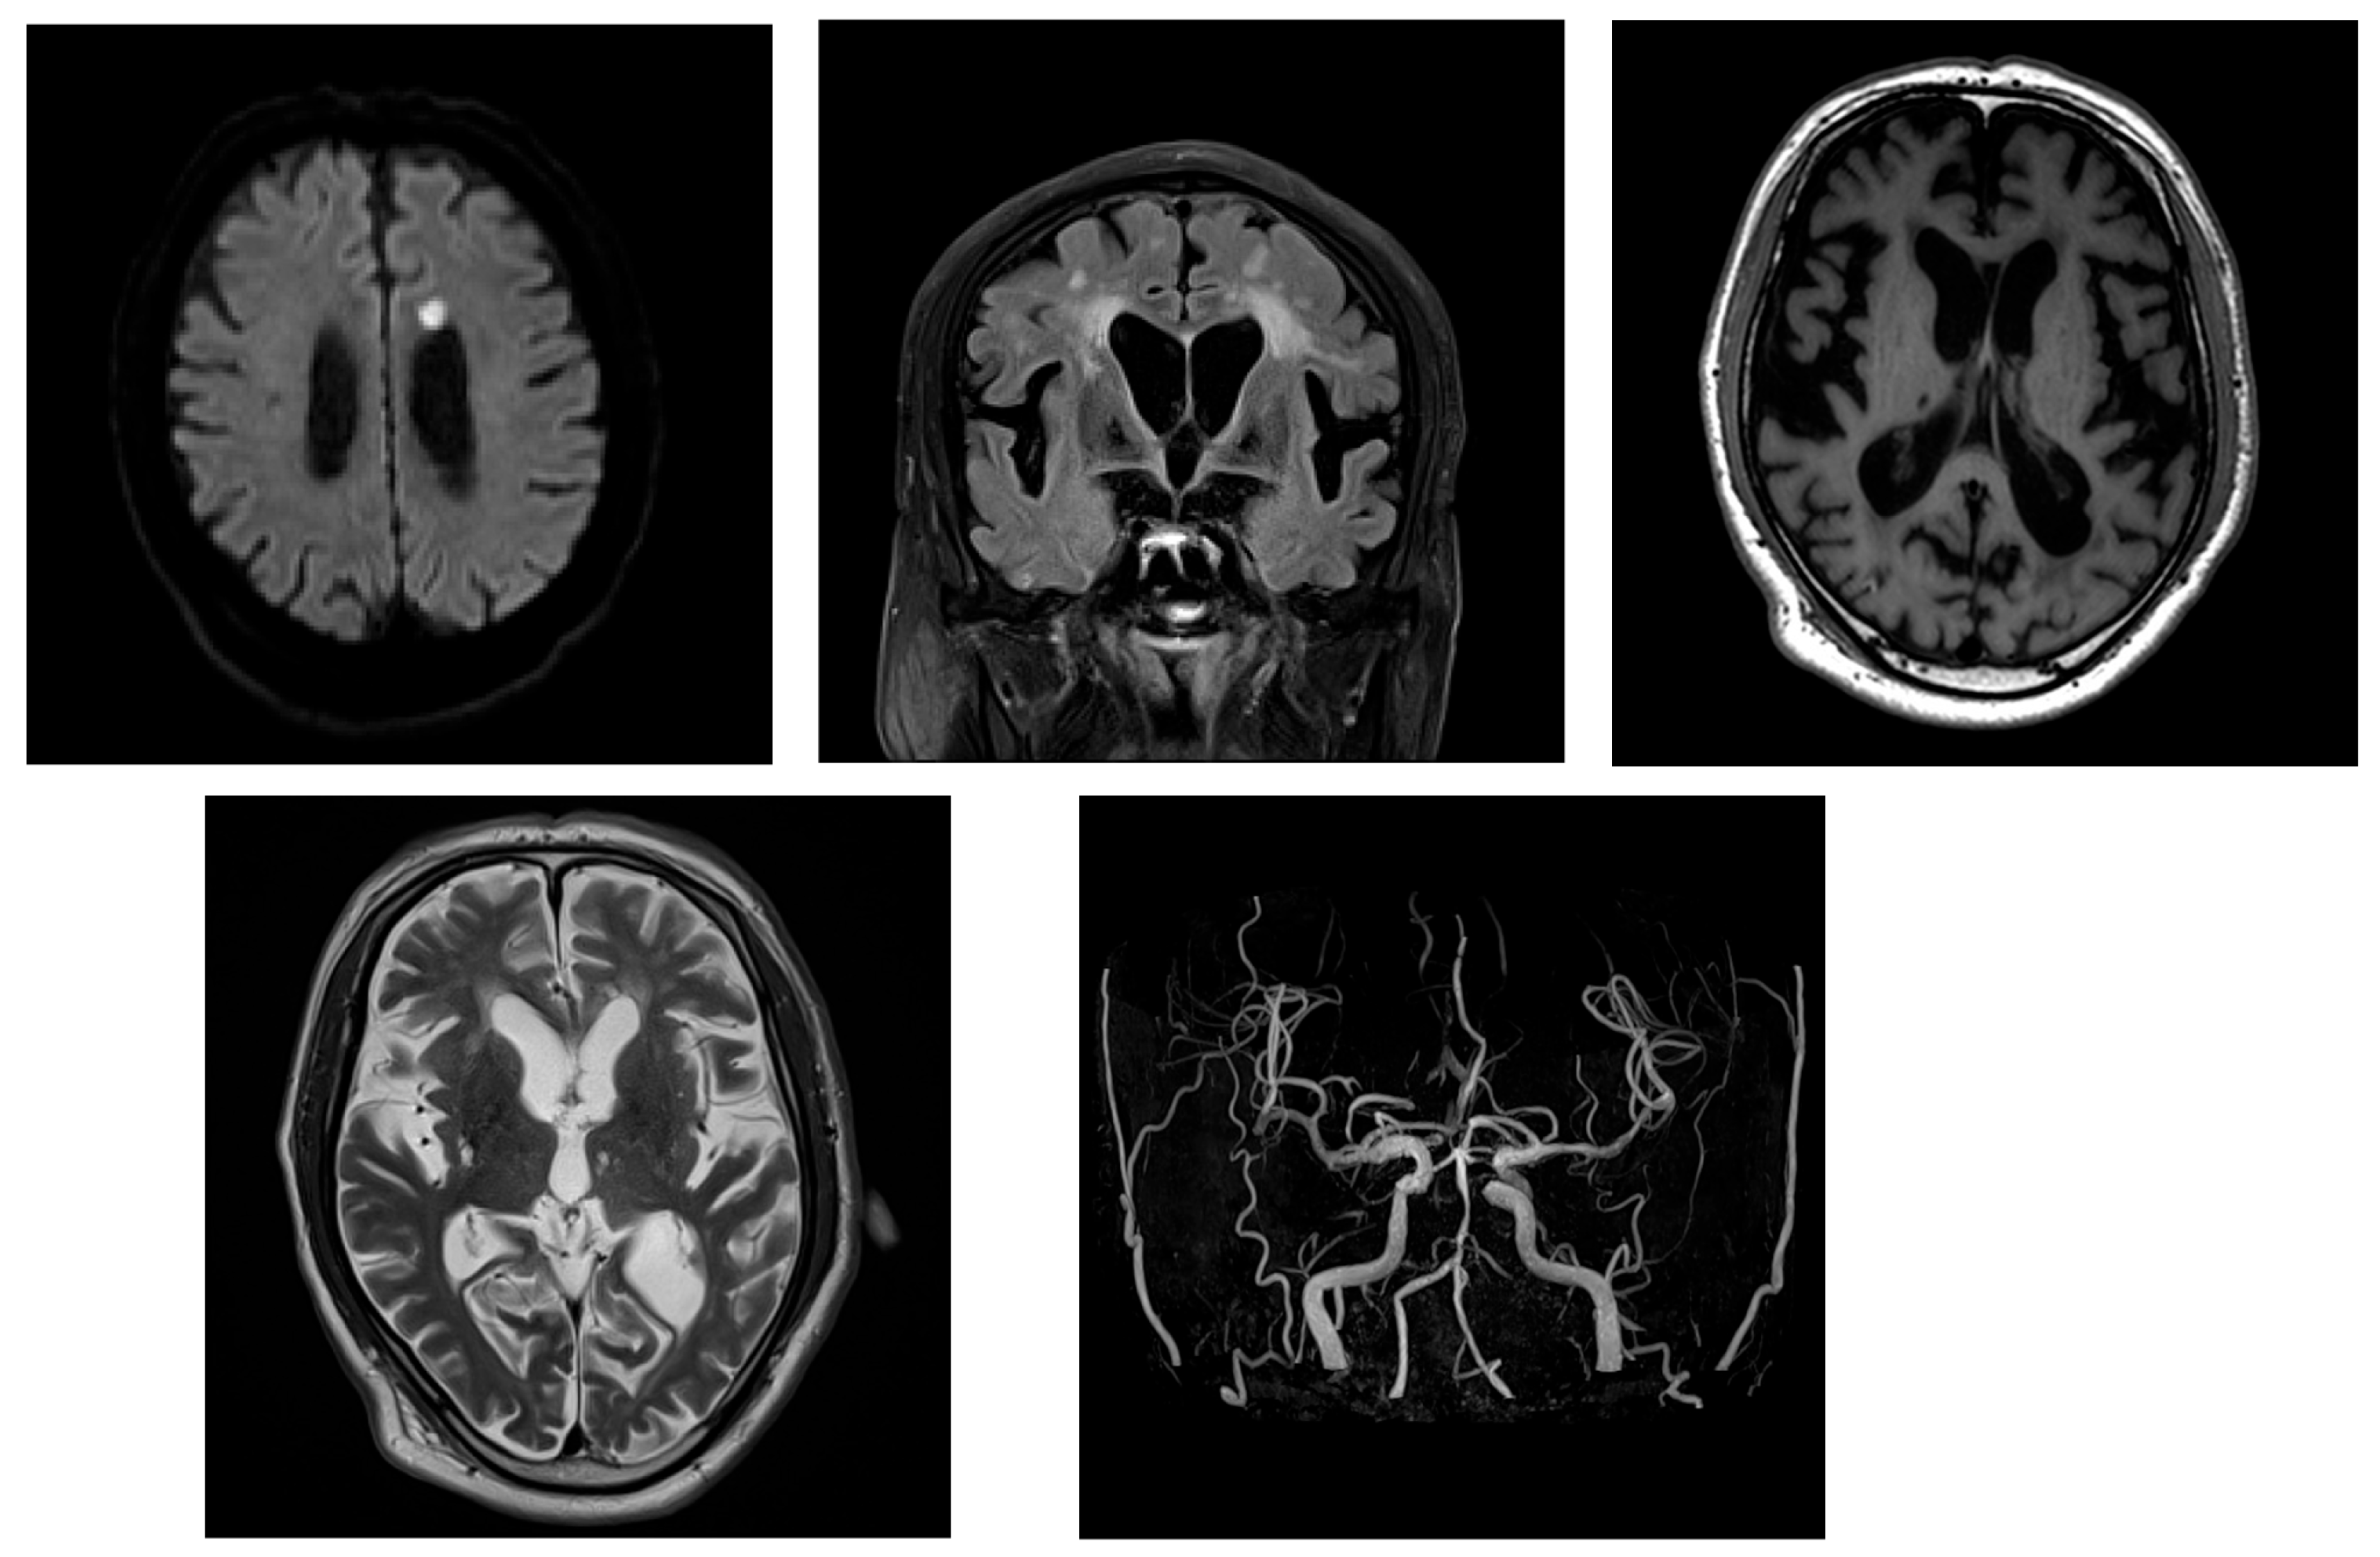

2.2. Case 2